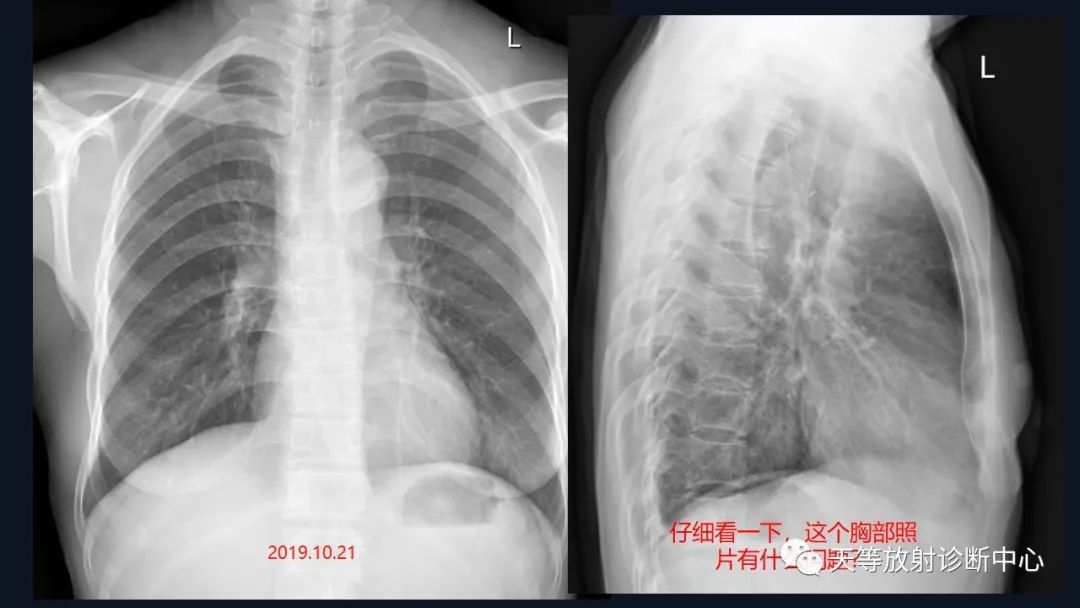

主 诉:发现左侧颈部隆起1周。

现病史:诉于2019年10月14日在无明显诱因下出现左侧颈部隆起,无疼痛,无咳嗽、咳痰,无发热、声嘶,无鼻塞、流涕,无鼻出血、抽吸性血痰,无耳鸣、耳漏,无头晕、头痛,无呼吸困难、吞咽困难等。病后曾自行服药及在当地输液治疗(具体不详),颈部隆起无变化,亦无红肿热痛表现。今日我院就诊,门诊医师遂拟”颈部肿物”收住入院。病后患者精神、睡眠、食欲欠佳,二便正常,体重无减轻。

结合颈部、胸廓入口区及腋窝多发淋巴结肿大并相互融合。

综合考虑淋巴瘤